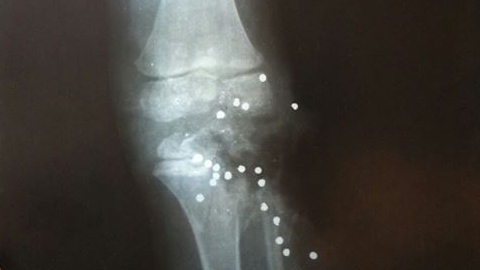

Напомним, по версии следствия, 22 июня Тимофей находился вместе с отцом, его другом и своим девятилетним старшим братом. У друга семьи с собой было огнестрельное оружие. Отец передал ствол старшему сыну, чему хозяин не воспрепятствовал, и мальчик, балуясь, выстрелил брату в ногу. Коленный сустав малыша оказался полностью разрушен. Теперь  ребенку предстоит очень длительное лечение - как рассказывала мать, до 20 лет ему предстоит пережить множество операций.

Сегодня корреспондент Saratovnews связался с отцом ребенка и сообщил более точную информацию. Одна из серьезнейших проблем - выстрелом были разрушены эпифизы длинных трубчатых костей ноги, в которых располагаются "точки роста". Каждые два года Тимофею предстоят операции для того, чтобы искусственно удлиннять кость, иначе нога просто не будет расти.